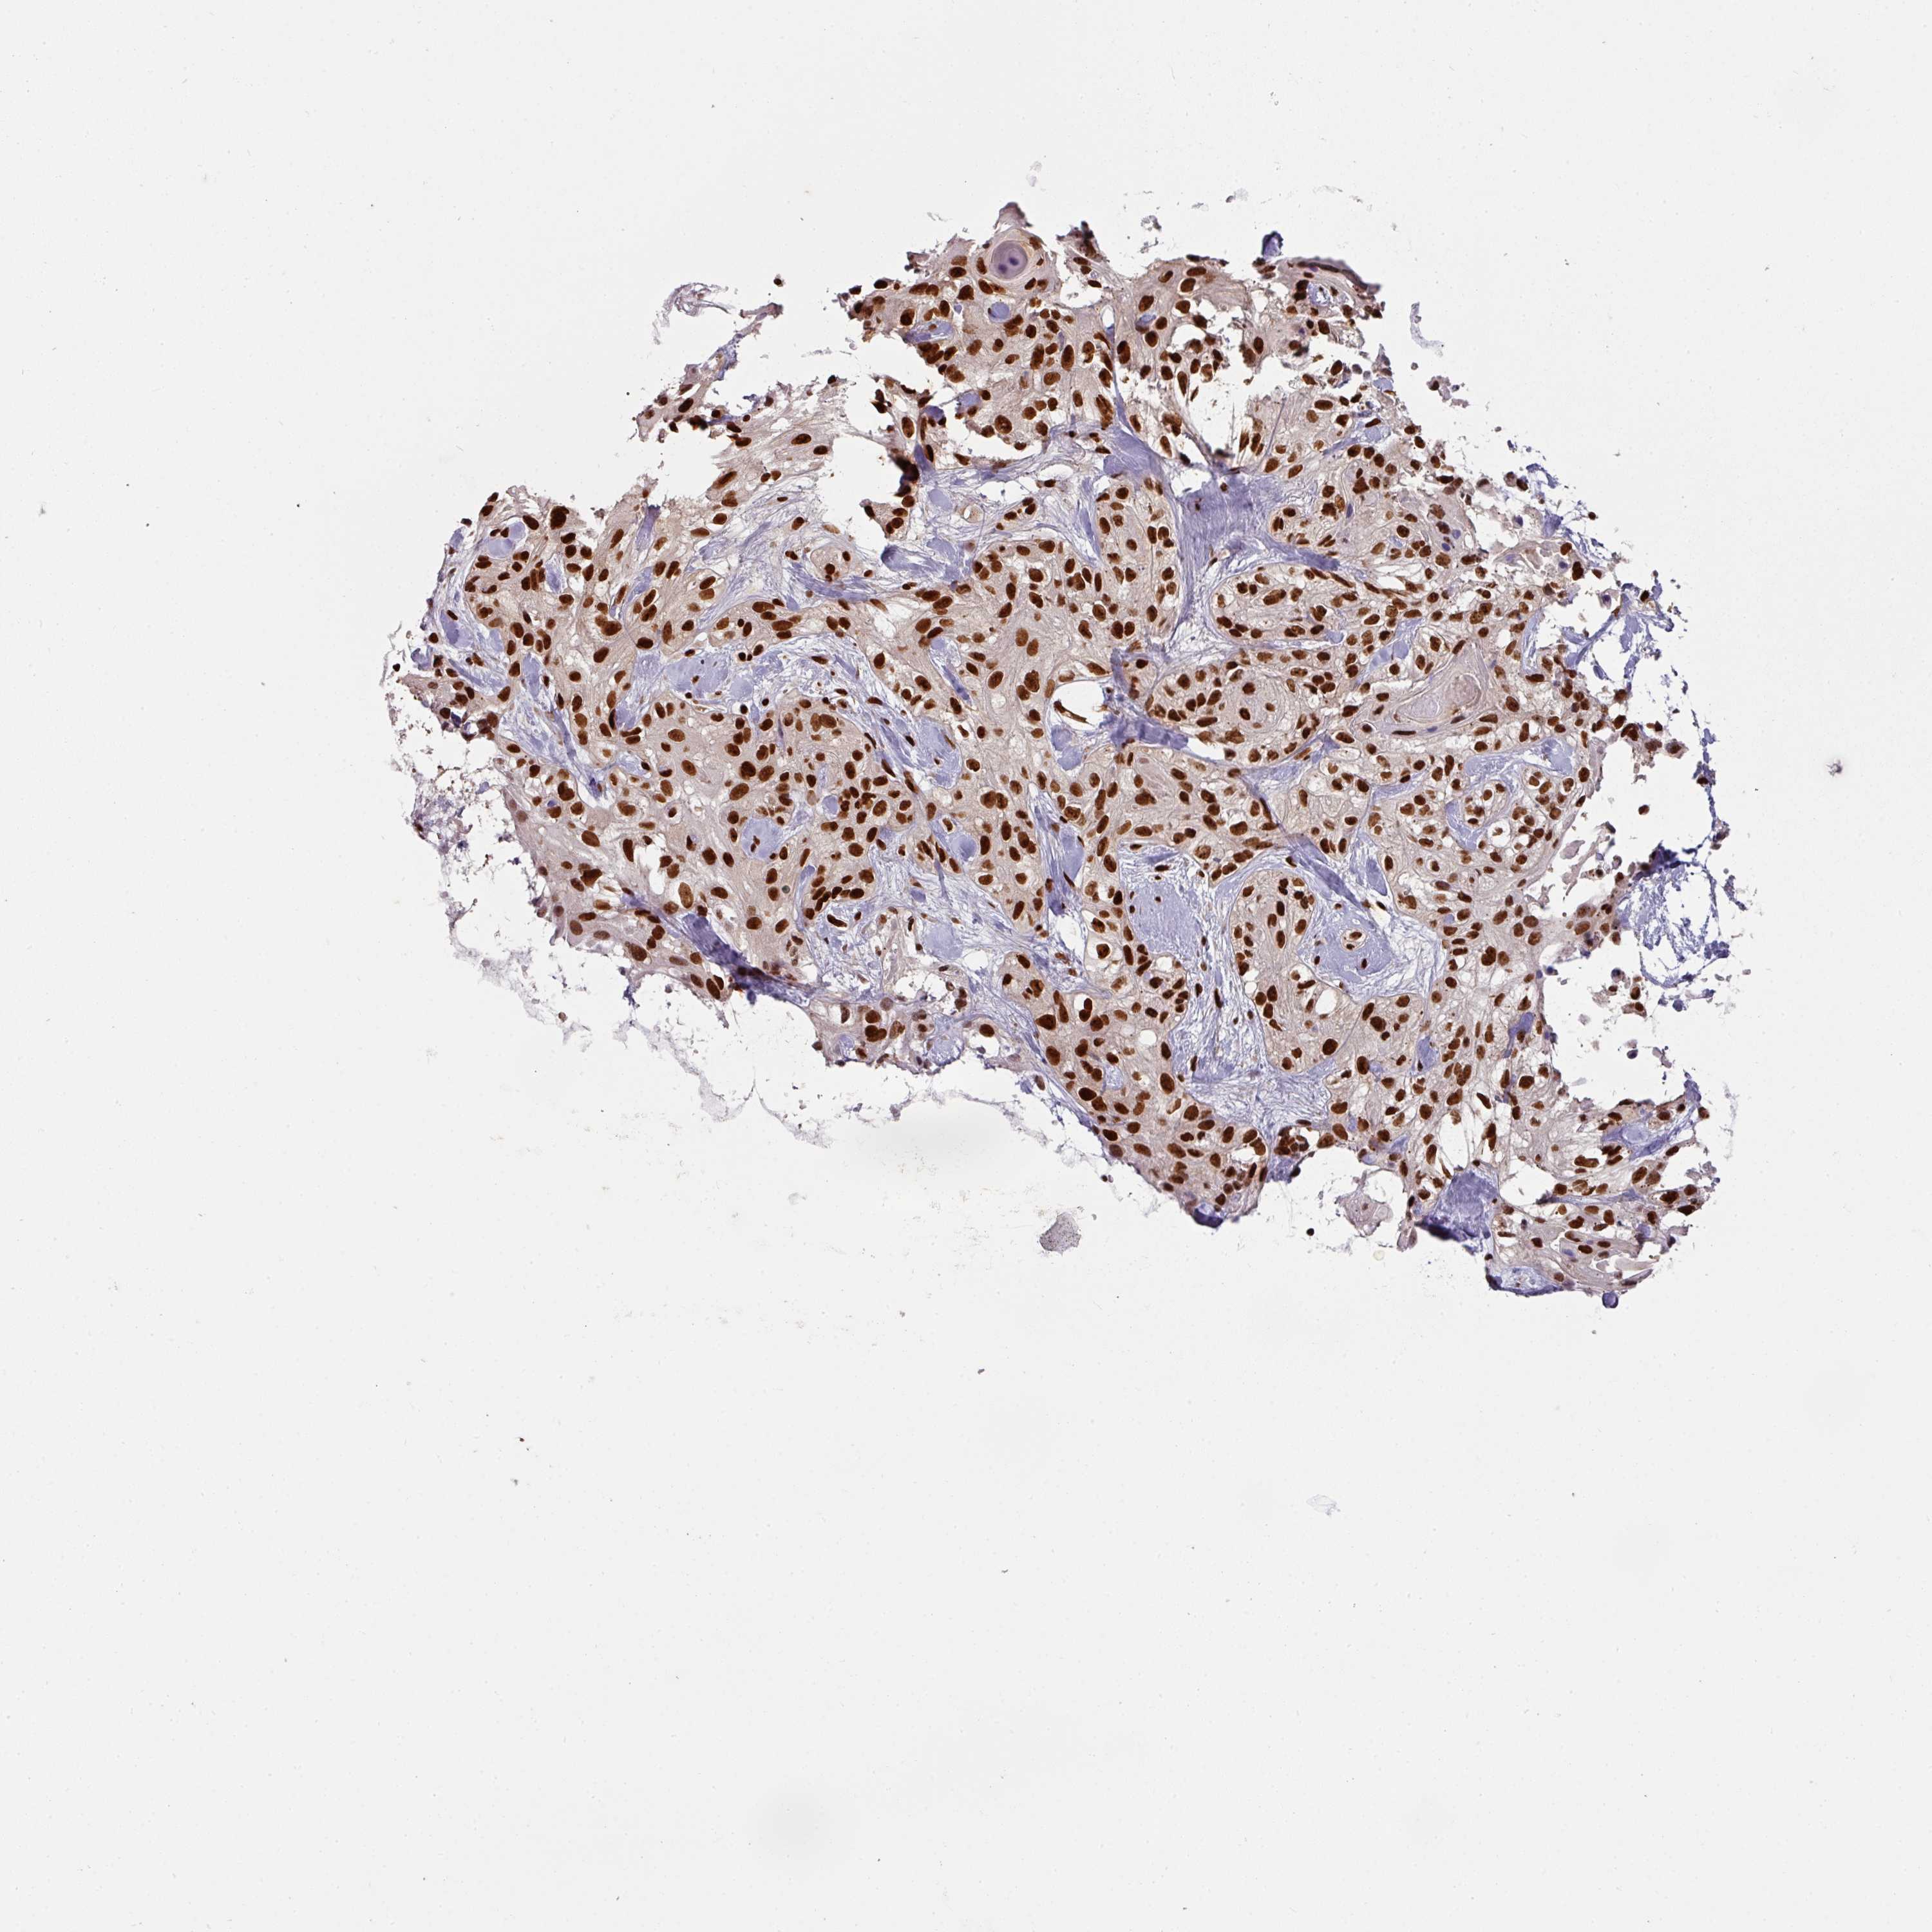

SKIN CANCER - Protein expressioni

A mouse-over function shows sample information and annotation data. Click on an image to view it in a full screen mode. Samples can be filtered based on level of antibody staining by selecting one or several of the following categories: high, medium, low and not detected. The assay and annotation is described here.

Antibody stainingi

Antibody staining in the annotated cell types in the current human tissue is reported as not detected, low, medium, or high, based on conventional immunohistochemistry profiling in selected tissues. This score is based on the combination of the staining intensity and fraction of stained cells.

Each image is clickable and will lead to virtual microscopy that enables deeper exploration of all samples and also displays staining intensity scores, fraction scores and subcellular localization as well as patient and tissue information for each sample.

Antibody HPA045245

Basal cell carcinoma